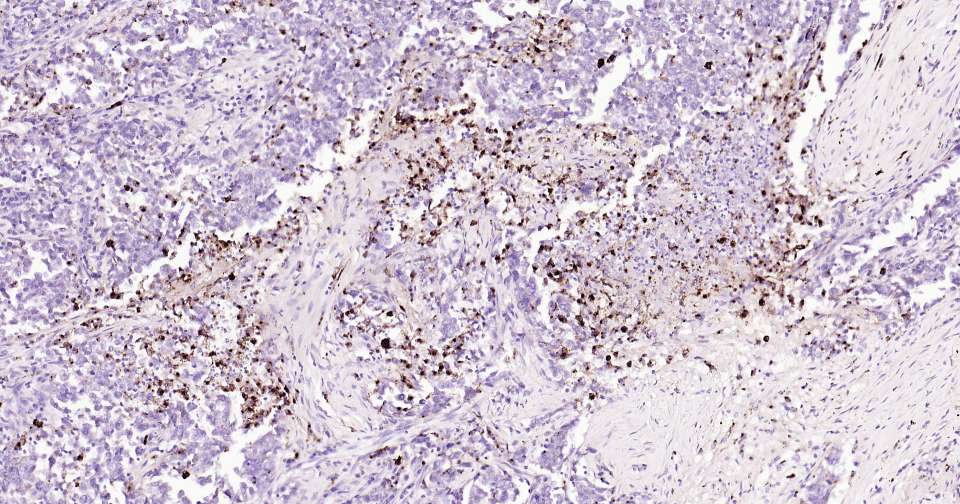

Immunohistochemical analysis of paraffin embedded human pancreatic cancer tissue slide using IHC0343H (Human Osteopontin Kit).

Immunohistochemical analysis of paraffin embedded human pancreas tissue slide using IHC0343H (Human Osteopontin Kit).

Immunohistochemical analysis of paraffin embedded human kidney tissue slide using IHC0343H (Human Osteopontin Kit).

Immunohistochemical analysis of paraffin embedded human brain tissue slide using IHC0343H (Human Osteopontin Kit).

Immunohistochemical analysis of paraffin embedded human lung cancer tissue slide using IHC0343H (Human Osteopontin Kit).